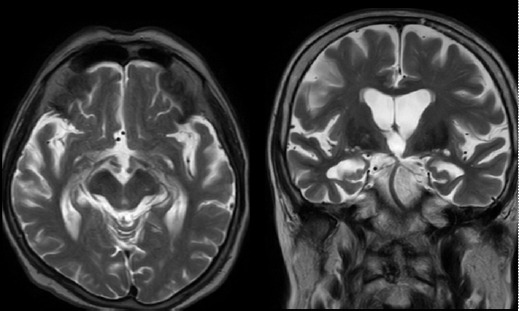

Alzheimer disease (AD) is the most common cause of dementia worldwide. Its clinical manifestations include a progressive loss of memory and other cognitive domains, as well as brain atrophy. An elevated homocysteine level (>15 µmol/L), known as hyperhomocysteinemia, is also an attributing risk factor for AD, vascular pathologies, and brain atrophy. Neuroimaging studies including T2-weighted magnetic resonance imaging scans revealed white matter hyperintensities in the periventricular and deep white matter, enlarged ventricles, widened sulci, and decreased white matter mass, which are features of aging, as well as cerebrovascular changes. This case series investigated changes in biochemical marker levels including serum homocysteine, folate, and vitamin B12, and the degree of atrophic variations in cortical-subcortical white matter in AD. The present study hypothesized that serum homocysteine levels might be used as a surrogate marker to screen for AD at an earlier stage.

Abstract Image

阿尔茨海默病(AD)是全球最常见的痴呆症病因。其临床表现包括记忆力和其他认知能力的逐渐丧失,以及脑萎缩。同型半胱氨酸水平升高(>15 µmol/L),即高同型半胱氨酸血症,也是导致老年痴呆症、血管病变和脑萎缩的一个危险因素。包括 T2 加权磁共振成像(MRI)扫描在内的神经影像学研究显示,脑室周围和深部白质中存在白质高密度(WMH),脑室扩大,脑沟增宽,白质质量减少,这些都是衰老以及脑血管变化的特征。本系列病例研究了 AD 患者血清同型半胱氨酸、叶酸和维生素 B12 等生化标志物水平的变化,以及皮质-皮质下白质萎缩变异的程度。本研究假设,大脑中的血清同型半胱氨酸水平可作为一种替代标志物,用于早期筛查 AD。